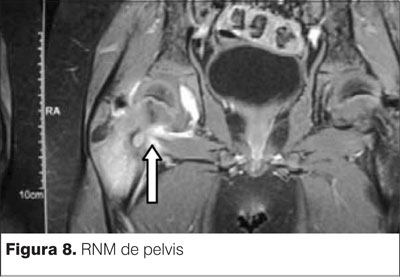

RNM informa asimetría en T2. Se observa claramente la lesión tumoral apoyada sobre la cortical posterior del cuello de fémur derecho (figuras 6, 7 y 8).